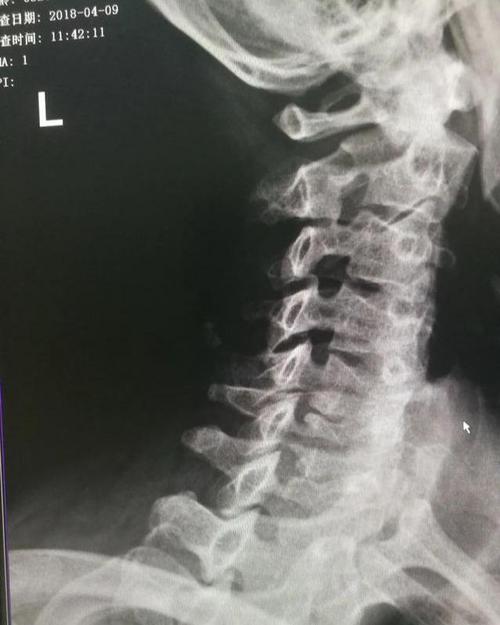

神经根型颈椎病图片

神经根型颈椎病图片,交感型颈椎病图片

神经根型颈椎病

颈椎病图片

严重颈椎病图片

颈椎病图片症状